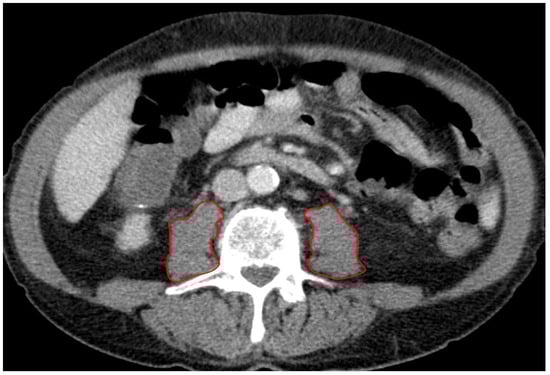

A board-certified radiologist blinded to all clinical data assessed the PMA (mm2) using a stationary workstation with dedicated software (Deep Unity Diagnostics 1.1.1.1, Dedalus Healthcare, Milan, Italy). Measurements were obtained from axial CT scans of the abdomen and pelvis during the portal venous phase, using a soft tissue kernel with a slice thickness of 3 mm and a reconstruction interval of 2 mm. The PMA was assessed in all patients at the level of the superior endplate of the third lumbar vertebra (L3) by manually tracing the right and left psoas muscles (Figure 1). The total PMA was calculated by adding the areas of both the left and right psoas muscles. Furthermore, the total PMA was adjusted for the patient’s body surface area (BSA), which was calculated using the Dubois formula: BSA = 0.007184 × height^0.725 × weight^0.425 (BSA: m2). This produced the indexed PMA (PMAi: mm2/m2).

Figure 1. Radiological measurement of PMA. Figure 1 demonstrates the measurement of left and right PMA by manually tracing the perimeter of the psoas muscles on an axial CT scan. The combined areas of the left and right muscles, adjusted for BSA, provided the PMAi.